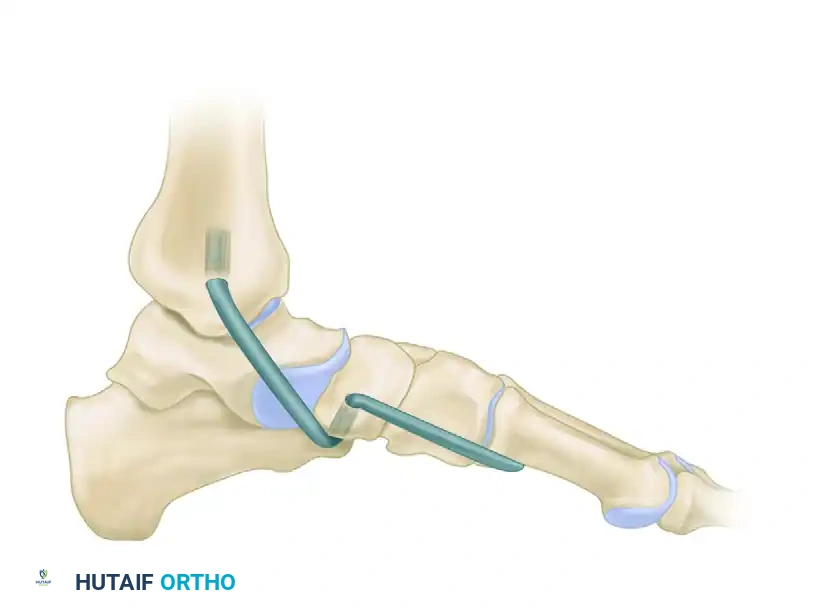

3. The Osteotomy

- Identify the calcaneocuboid joint line using a Keith needle or fluoroscopy.

- Perform the osteotomy 1.0 to 1.5 cm proximal to the articular surface of the calcaneocuboid joint using an oscillating sagittal saw.

- Trajectory: Aim the saw carefully between the anterior facet and the middle facet of the calcaneus.

Surgical Pitfall: Do not plunge the saw blade through the medial cortex. Overpenetration risks catastrophic injury to the medial soft tissues, specifically the medial plantar nerve and artery, as well as the FHL tendon. Complete the medial cortex osteotomy with a sharp osteotome.

4. Distraction of the Osteotomy

- Distract the osteotomy site using a combination of manual adduction of the forefoot and mechanical distraction.

- Place two 3/32-inch Steinmann pins: one into the anterior process (distal fragment) and one into the anterior body of the calcaneus (proximal fragment).

- Apply a hinged cervical lamina spreader (smooth or with very small teeth) between the pins or directly into the osteotomy to gently open the lateral column.